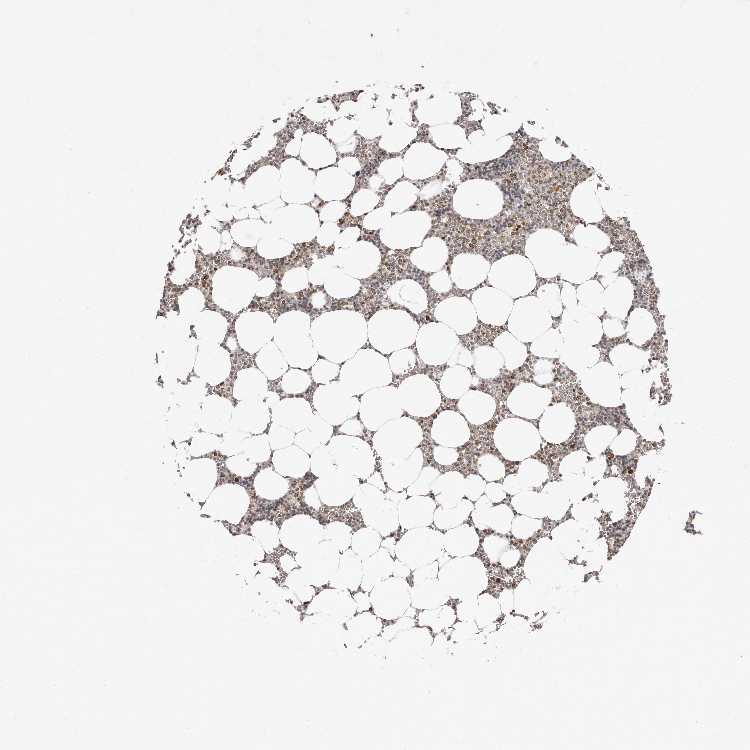

TISSUE PRIMARY DATA BONE MARROW Show tissue menu

BONE MARROW - Antibody stainingi

Antibody staining in the annotated cell types in the current human tissue is reported as not detected, low, medium, or high, based on conventional immunohistochemistry profiling in selected tissues. This score is based on the combination of the staining intensity and fraction of stained cells.

Each image is clickable and will lead to virtual microscopy that enables deeper exploration of all samples and also displays staining intensity scores, fraction scores and subcellular localization as well as patient and tissue information for each sample.

Antibody HPA027896Antibody HPA027897Antibody HPA027898

Hematopoietic cells MediumMediumMedium